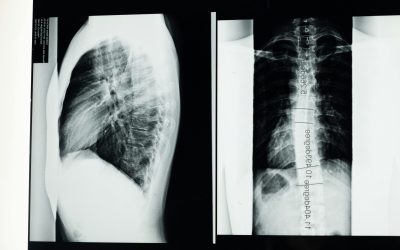

Can an X-Ray Show a Herniated Disc?

If you're dealing with back pain, numbness, or tingling, you might be wondering if an X-ray can show a herniated disc. After all, X-rays...